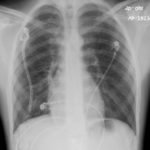

Initial chest radiograph showed a 50% right-sided pneumothorax with no mediastinal shift, which can be identified by the sharp line representing the pleural lung edge (see arrows) and lack of peripheral lung markings extending to the chest wall. While difficult to accurately estimate volume from a two-dimensional image, a 2 cm pneumothorax seen on chest radiograph correlates to approximately 50% volume.1 The patient underwent insertion of a pigtail pleural drain on the right and repeat chest radiograph showed resolution of previously seen pneumothorax. Ultimately the pigtail drain was removed and chest radiograph showed clear lung fields without evidence of residual pneumothorax or pleural effusion.